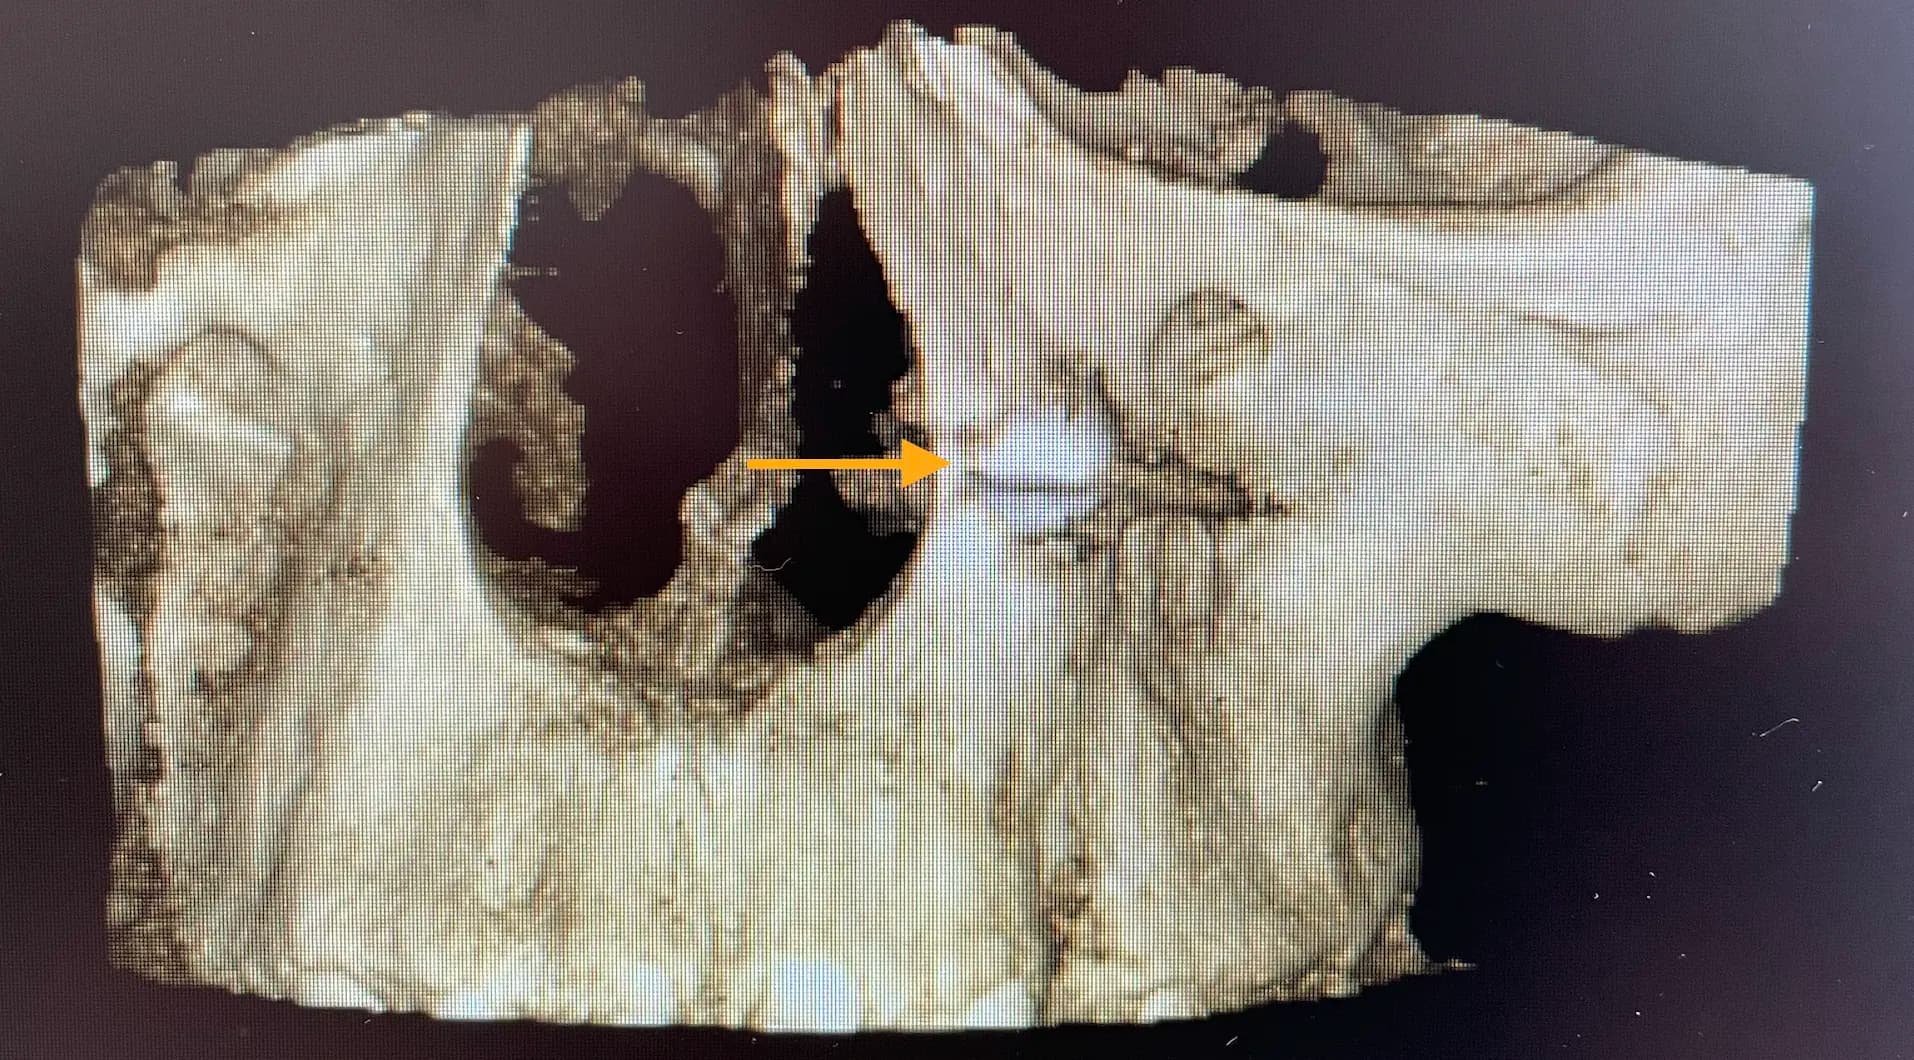

Exposure and traction of impacted teeth are surgical procedures performed to help an impacted tooth properly erupt through the gums and into its normal position in the dental arch. Before the procedure, the surgeon performs a thorough evaluation of the situation using simple or 3D dental x-rays to determine the exact position of the impacted tooth, its orientation, and its relationship to adjacent teeth and surrounding structures. Based on the evaluation, a treatment plan is developed to expose the impacted tooth and allow it to erupt through the gums. After exposing the impacted tooth, an orthodontic appliance may be attached to the tooth to help guide its eruption through the gums and into its proper position in the dental arch. Subsequently, light and controlled force is applied to the impacted tooth to gradually guide it through the gums and into its final position in the dental arch.